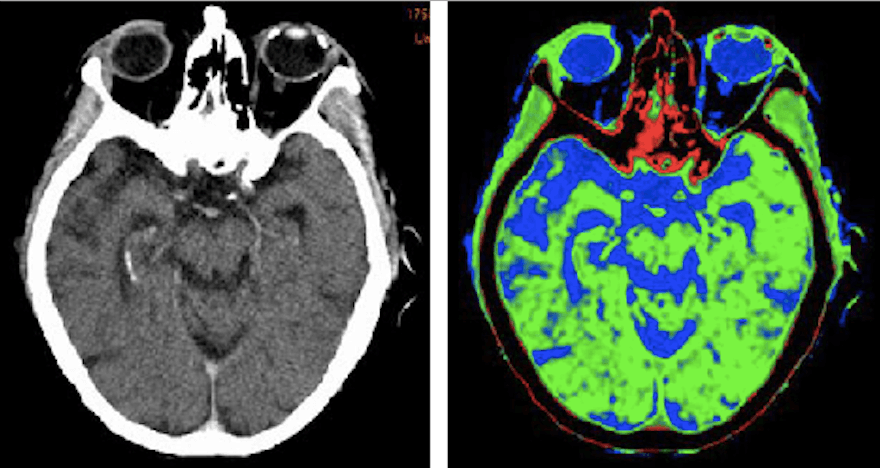

Whereas the previous examples on this list dealt with outlining the outer edges or boundaries of an object, semantic segmentation is much more precise and specific. Semantic segmentation is the process of associating every single pixel in an entire image with a tag. With projects requiring semantic segmentation, human annotators will usually be given a list of pre-determined tags to choose from with which they must tag everything on the page.

Using similar platforms used in polygonal annotation, annotators would draw lines around a group of pixels they want to tag. This can also be done with AI-assisted platforms where, for example, the program can approximate the boundaries of a car, but might make a mistake and include the shadows underneath the car in the segmentation. In those cases, human annotators would use a separate tool to crop out the pixels that don’t belong. For example, with training data for autonomous vehicles, annotators might be given instructions like, “Please segment everything in the image by roads, buildings, cyclists, pedestrians, obstacles, trees, sidewalks and vehicles.”

Another common application of semantic segmentation is medical imaging devices. For anatomy and body part labeling, annotators are given a picture of a person and told to tag each body part with the correct body part names. Semantic segmentation can also be used for incredibly specialized tasks like tagging brain lesions within CT scan images.

Via semanticscholar.org, original CT scan (left), annotated CT scan (right).